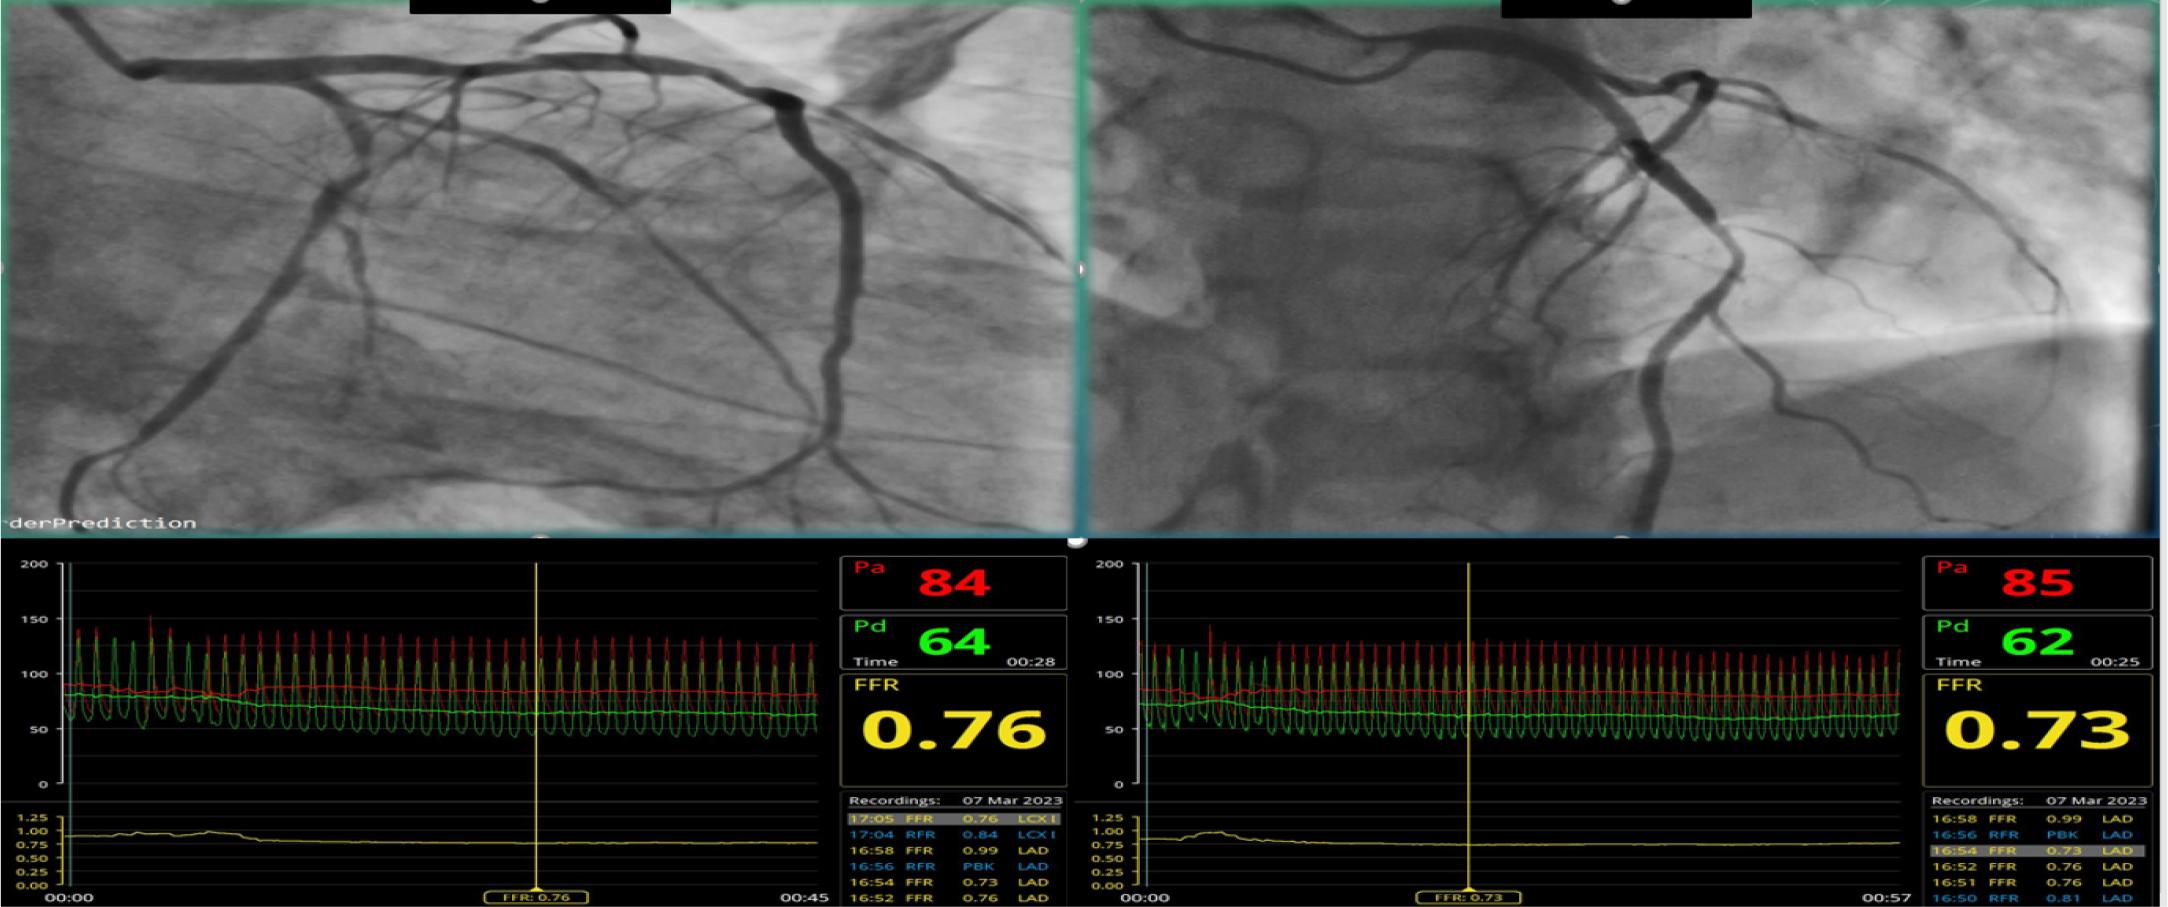

Coronary angiography revealed subocclusion of the middle segment of the obtuse marginal artery (OM1). The left anterior descending artery (LAD) exhibited a 50% stenosis in the middle segment that was deemed significant based on fractional flow reserve (FFR) measurement. Additionally, the proximal segment of the left circumflex artery (LCx) showed a 50-60% stenosis, which was also determined to be hemodynamically significant based on FFR. Coronary angioplasty was performed with three drug-eluting stents in the middle LAD, proximal LCx, and middle OM1. (Fig. 2A and Fig. 2B)

Coronary angiogram and FFR measurements – subocclusion of OM 1 (middle segment); 50 % middle LAD stenosis (FFR – 0.73); 50-60 % proximal LCx stenosis (FFR – 0.76)